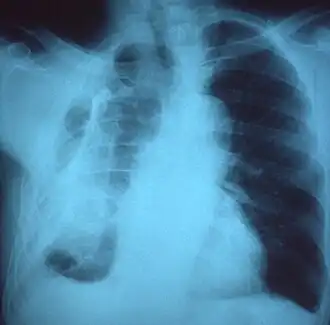

Fibrotórax extenso do lado esquerdo

Radiografia de tórax exibindo opacificação não homogênea da metade esquerda do tórax que é fibrotórax